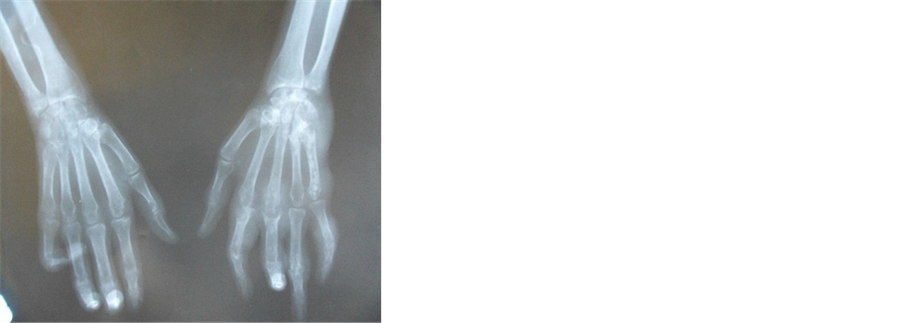

The X-ray of the hands, the front feet and the left knee objectified a stern destructive gouty arthropathy (Figure 2). At the right knee, they showed a stern septic synovitis with complete disappearance of the joint spacing, important diffuse demineralization and erosion of the external tibial tray (Figure 3). The MRI of the right knee confirmed arthritis with articular spring (Figure 4).

Figure 2. X-ray of two face’s hands and wrists giving prominence to a severe destructive gouty arthropathy and tophus.